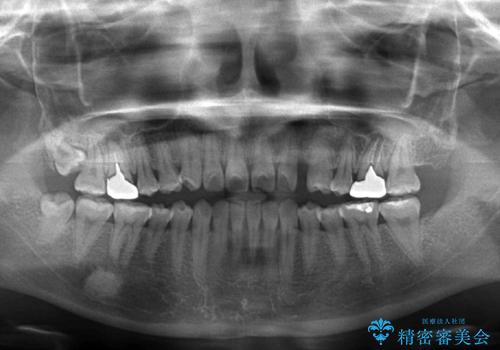

- 前歯の開咬と、受け口による咬み合わせの悪さを気にして来院された患者様です。

左上は後続永久歯の欠損によりスペースがあり、矯正治療と並行してインプラントあるいはブリッジによる補綴治療が必要な状況でした。

上顎歯列が狭窄していたため、急速拡大装置により上顎骨を側方に拡大し、その後インビザラインにて矯正治療を行うこととしました。

矯正治療と並行してインプラントによる補綴治療を行うこととしました。